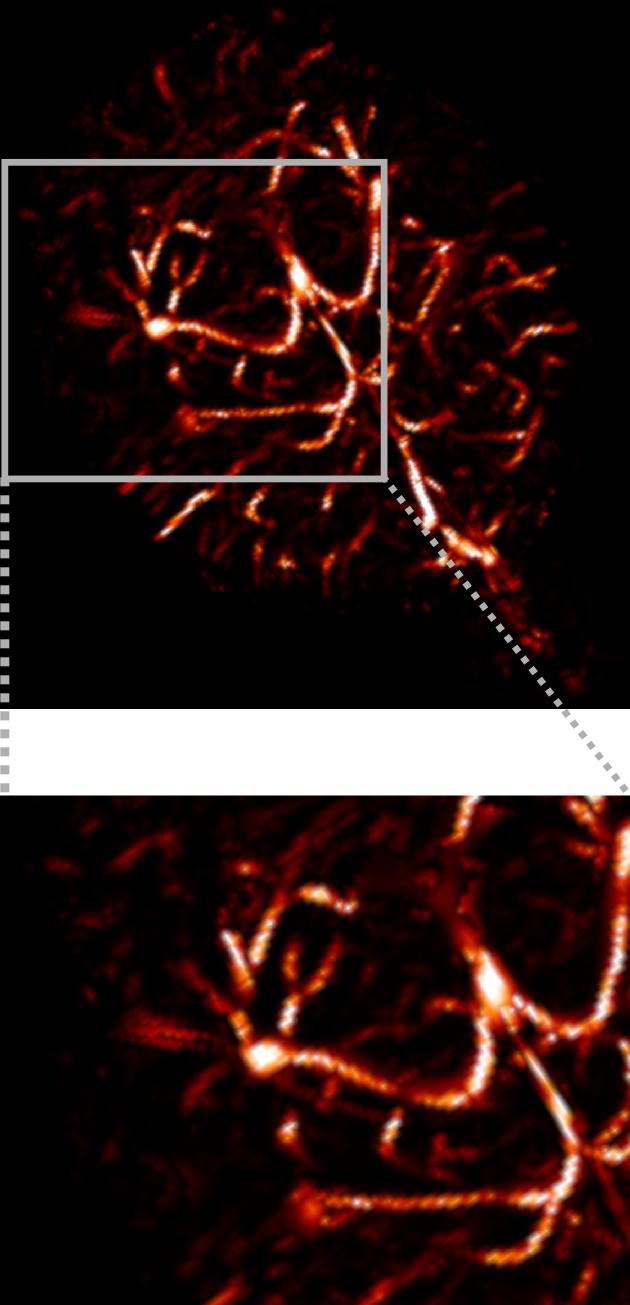

3.2.2 3D angiography

Using the same method as in 2D, namely TSP-sampling and projection onto the set of constraints, we reconstructed volumes from 3D -space. In order to estimate the quality of the reconstructions, we compared the angiograms computed from the 3D images using Frangi filtering [19]. The results are shown in Fig. 3 for acceleration factors (Fig. 3(b,e)) and (Fig. 3(c,f)) and compared to the angiogram computed from the whole data.

Using the strategy described in Part 3.1 the time to traverse -space would be 3.53 s (full acquisition), 3.15 s () and 0.88 s (). The main drawback of TSP-based sampling schemes is that the time reduction is not directly proportional to , in contrast to classical 2D downsampling and reading out along the third dimension. Nevertheless, if the number of measurements is fixed, the TSP-based approach leads to more accurate reconstruction results since the sampling scheme may fit any density [7].

Angiograms shown in Fig. 3 illustrate that one can reduce the travel time in the -space and still observe accurate microvascular structure. If , time reduction is minor (about 10% less), but the computed angiogram is almost the same as the one obtained with a complete -space. It is interesting to notice that with a higher acceleration factor (), the acquisition time is reduced by 75%, but the computed angiogram remains of good quality. The angiogram appears a bit noisier, especially in the pre-injection setting (Fig. 3(c)), but the post-injection image allows recovering Willis polygon and most of the major vessels of the mouse brain (Fig. 3(f)).

| Original (s) | (s) | (s) |

|---|---|---|

| (a) | (b) | (c) |

|

pre-injection

|

|

|

| PSNR=29.0 dB | PSNR=26.6 dB | |

| (d) | (e) | (f) |

|

post-injection

|

|

|

| PSNR=25.5 dB | PSNR=24.1 dB |